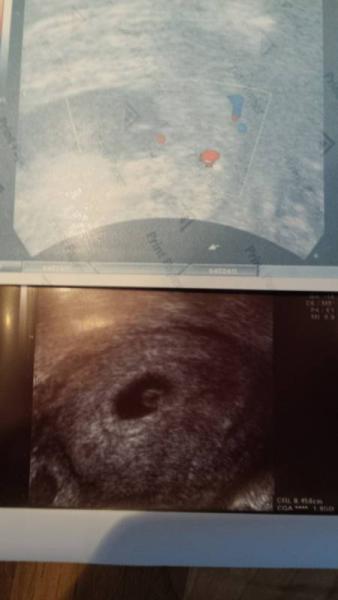

Aber wir haben es trotzdem gefunden. Zwischen Dottersack und Fruchthöhlenwand hat es sich's bequem gemacht. Aber sein Herzchen hat es verraten Schön zu sehen auf dem oberen Bild (der kleine rote Punkt links) Euch allen einen schönen Nikolaustag

Bild zu Krümelchen wollte Verstecken spielen - Forum für Juli - Mamis